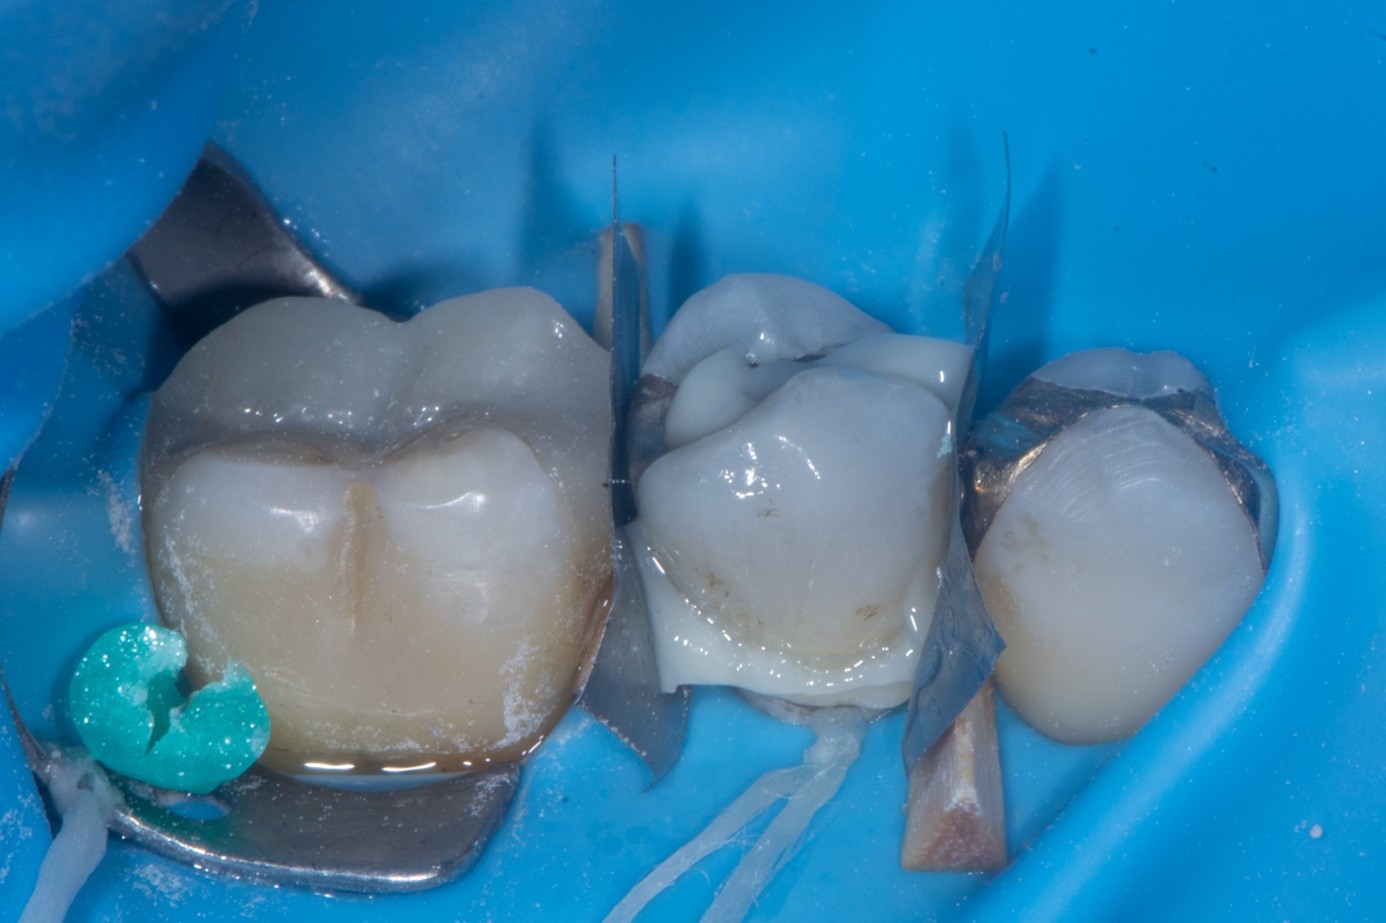

(21.) Intraoral view after rubber dam isolation, showing prepared surfaces: both sandblasted and etched, with silanization applied only to the composite surface, ready for reattachment.

Figure 21

(22.) Intraoral view after rubber dam isolation, showing prepared surfaces: both sandblasted and etched, with silanization applied only to the composite surface, ready for reattachment.

Figure 22

(23.) Intraoral view after rubber dam isolation, showing prepared surfaces: both sandblasted and etched, with silanization applied only to the composite surface, ready for reattachment.

Figure 23

(24.) Intraoral view after rubber dam isolation, showing prepared surfaces: both sandblasted and etched, with silanization applied only to the composite surface, ready for reattachment.

Figure 24

(25.) Correction and removal of composite excess, followed by light polymerization.

Figure 25

(26.) Correction and removal of composite excess, followed by light polymerization.

Figure 26